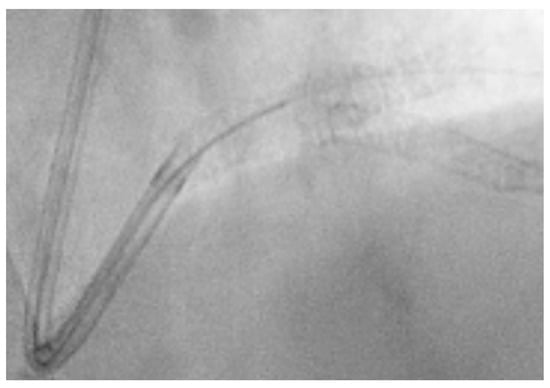

- Engage the left coronary artery with an EBU 4.0/8F guiding catheter. Wiring the three branches of the trifurcation (Floppy guide wires in LAD and RI, Hydrophilic guide wire in LCX) (Figure 14).